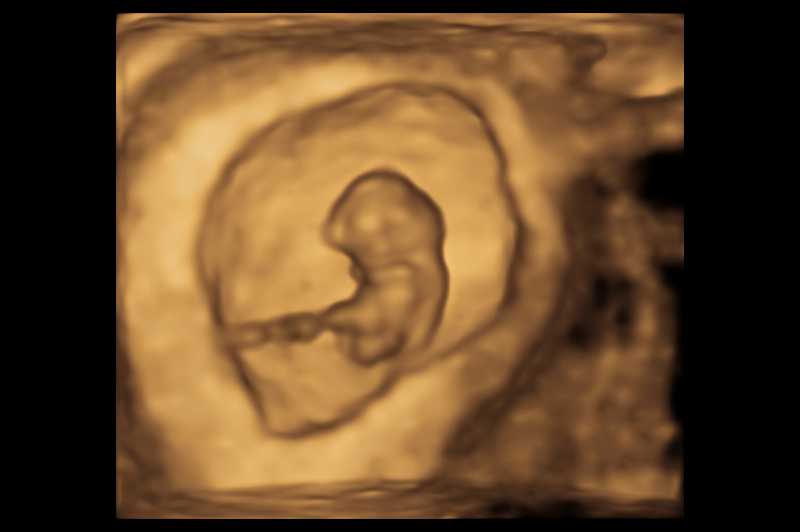

NIPT – Non-Invasive Prenatal Testing

Every expectant parent is anxious for reassurance that all is going well with the pregnancy. A blood test from the mother that can look at some of the genetic make-up of the developing foetus, and even tell you the gender, can be an informative step if desired. The NIPT is an optional test designed …